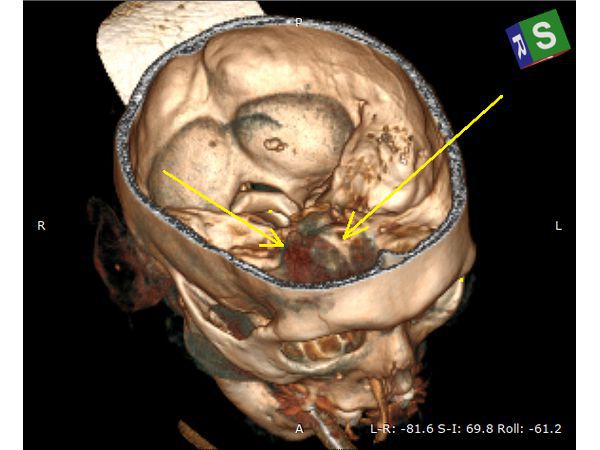

КТ головного мозга в первые сутки: выявлен линейный перелом лобной кости, переходящий на основание передней черепной ямки, и очаги ушиба полюсных отделов правой височной и лобной долей головного мозга (II вид по Корниенко), травматическое субарахноидальное кровоизлияние. Также выявлен двусторонний перелом нижней челюсти.

КТ головного мозга на вторые сутки: выявлена трансформация очага ушиба правой лобной доли во внутримозговую гематому (агрессивный очаг ушиба головного мозга).

Техническая сложность заключалась в широких лобных пазухах пациента, т. к. фрезевое отверстие весьма желательно было наложить, не вскрывая лобную пазуху, но в то же время непосредственно в проекции внутримозговой гематомы. Для этого выполнена предоперационная разметка проекции внутримозговой гематомы на свод черепа.

Предоперационная 3D-разметка позволила рассчитать доступ — непосредственно в проекции внутримозговой гематомы, но без вскрытия лобной пазухи.